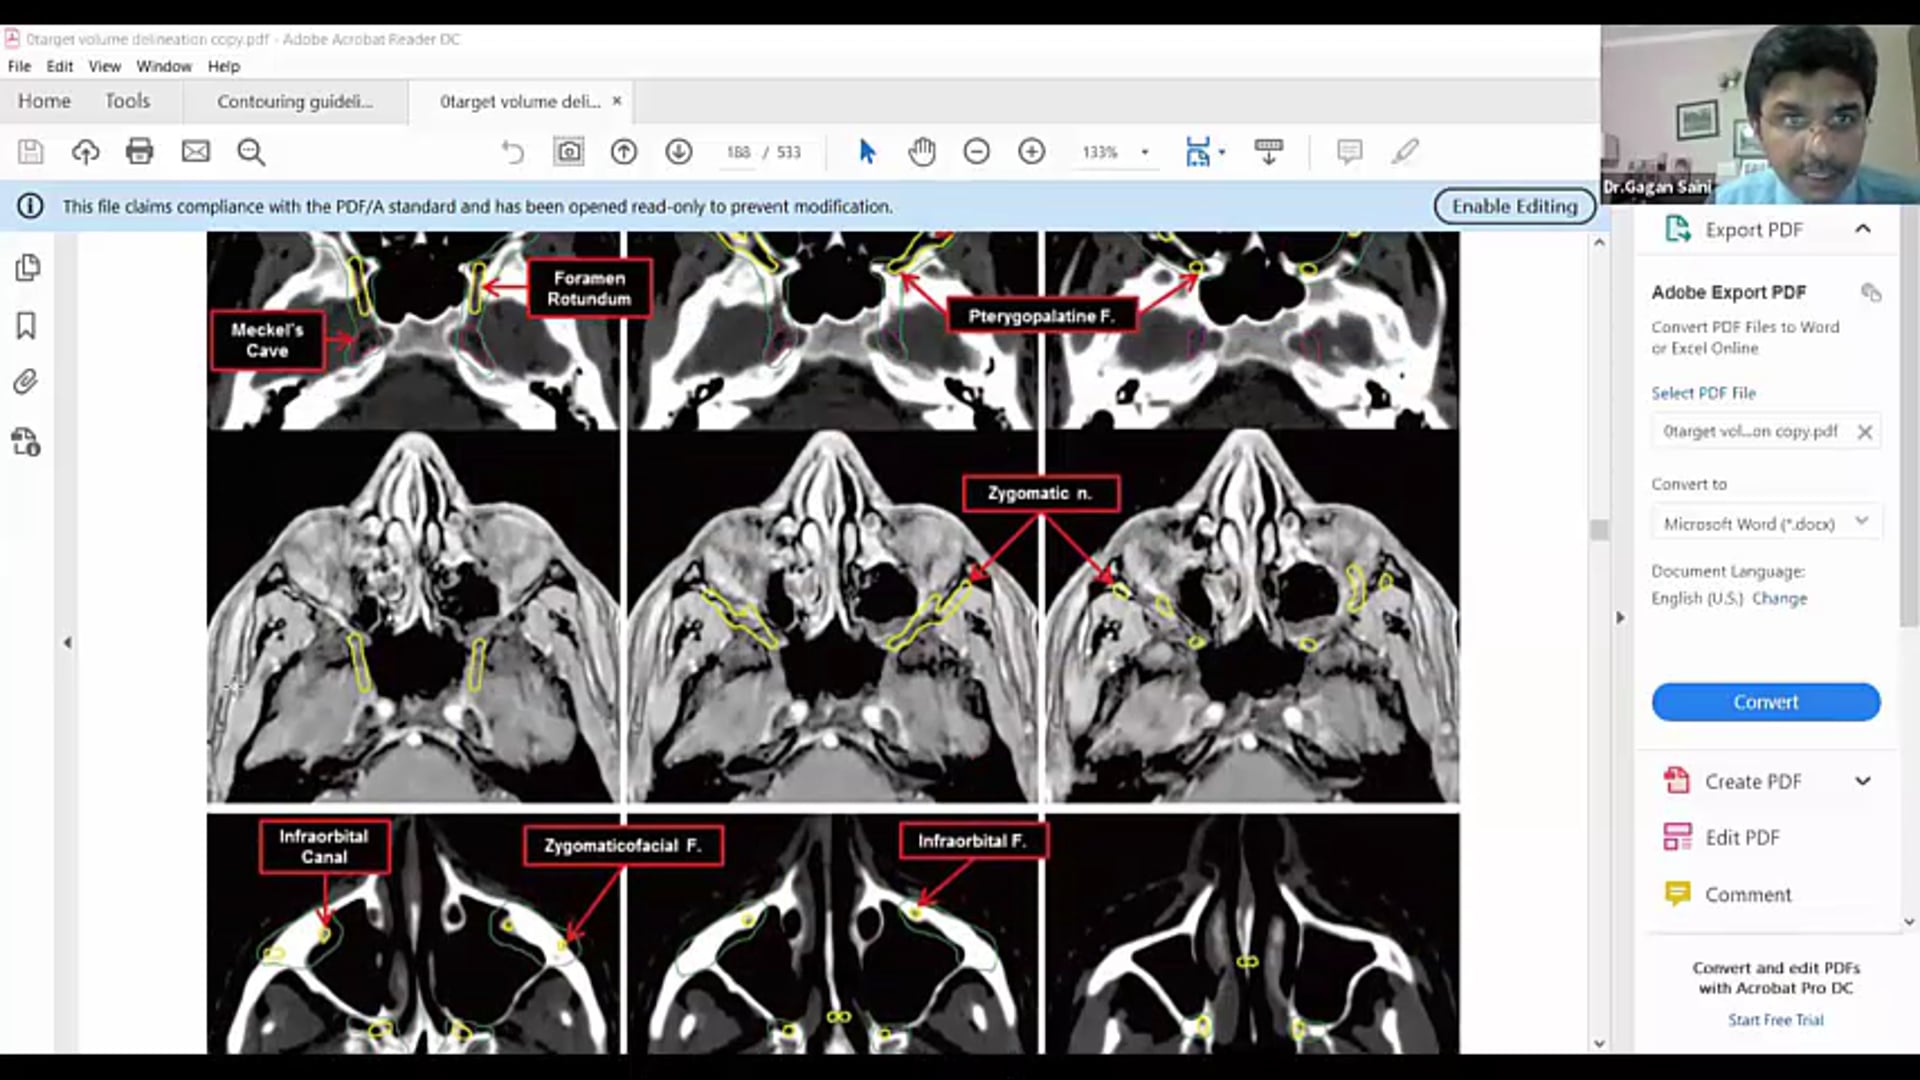

04/04/19 - Dr. Gagan Saini - Radiation Oncology - Head and Neck India

Management of Advanced Ca Oropharynx- Evidence & Target volume delineation, acquisition of the planning CT, treatment based and nodal category